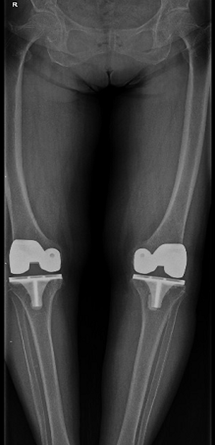

我科为国家中医药管理局“十二五”重点专科建设单位。拥有进口关节镜全套设备、髋膝肩肘人工关节置换全套体系、TDP治疗仪、电脑中频透热治疗仪、多功能微波治疗仪、中药煎药机、下肢功能锻炼机等诊疗设备。根据国内外关节外科发展方向,充分应用中医药发展优势,创立中西医结合特色。近年来已开展了髋、膝、肘、肩等关节人工置换术1000余例,每年各种关节置换100多例,各种关节镜微创手术、运动损伤致各种肌腱、韧带损伤修补重建手术200余例及各种关节骨折内固定手术近400余例,数量和质量居市内各大医院前列。本科室主持两项自治区科研课题两项,市科研6项,在国家杂志发表论文60余篇,研究了跌打散、郁金散、跌打郁金膏、驳骨膏、跌打追风酒、损伤外洗合剂等二十余种纯中药制剂,为满足患者术后快速康复需要,进一步开发了中药止痛贴、消肿贴、痛风贴等外用制剂,广泛运用临床。

①四肢骨关节疾患的人工关节置换及翻修治疗;

擅长中西医结合治疗骨科各种疑难疾病:骨质疏松、慢性腰腿痛、运动损伤、各种关节疾病、复杂关节内骨折、运动损伤、儿童骨骼发育异常等疾病。专长:髋、膝、肩等关节置换、翻修术,复杂关节骨折固定术、前后交叉韧带、半月板损伤、肩关节、踝关节等韧带重建微创手术。

擅长各种四肢骨关节疾病及运动创伤的治疗,各种四肢及复杂关节内骨折内固定术,尤其擅长各种人工关节置换术、翻修术及各种微创关节镜手术如膝关节交叉韧带重建、半月板损伤修复等治疗及基础、临床研究工作。

擅长半月板损伤、交叉韧带损伤、膝关节复杂多韧带损伤、肩袖损伤、复发性肩关节脱位、踝、肘、腕关节等各关节运动损伤的中西医治疗和关节镜微创手术技术;骨关节炎等各种骨关节疾病、复杂关节内骨折的诊治;四肢骨折手术治疗 ,人工关节置换术等。

擅长运用中西医对四肢、关节及脊柱疾病的诊断和治疗,对各种骨折切开复位内固定术、髋膝关节置换、关节镜微创手术、骨折脱位手法整复有一定的研究